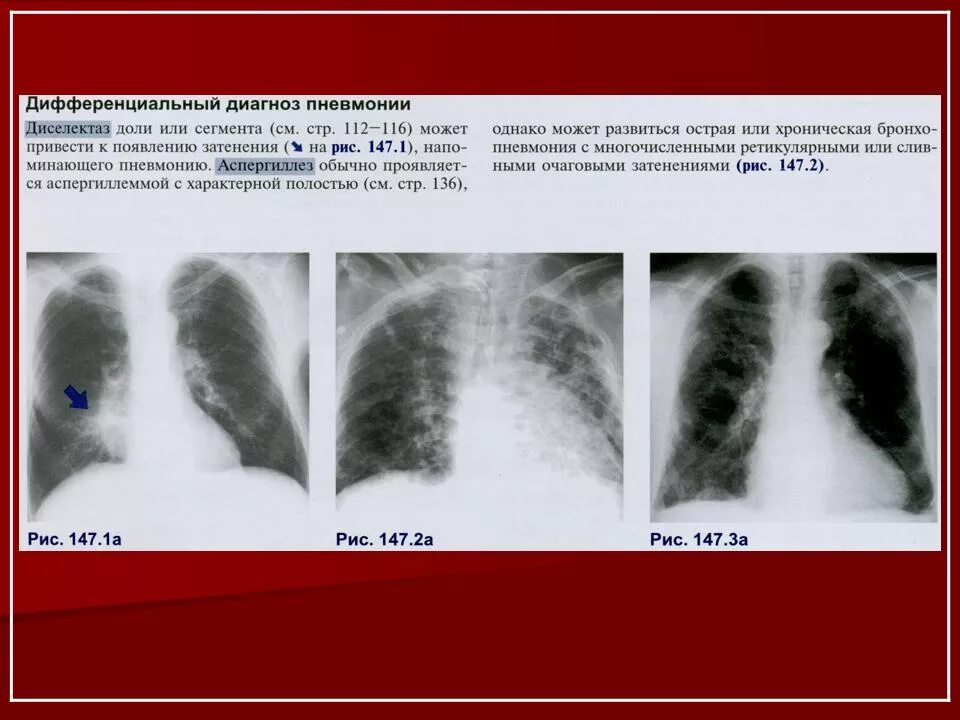

Как получить воспаление легких